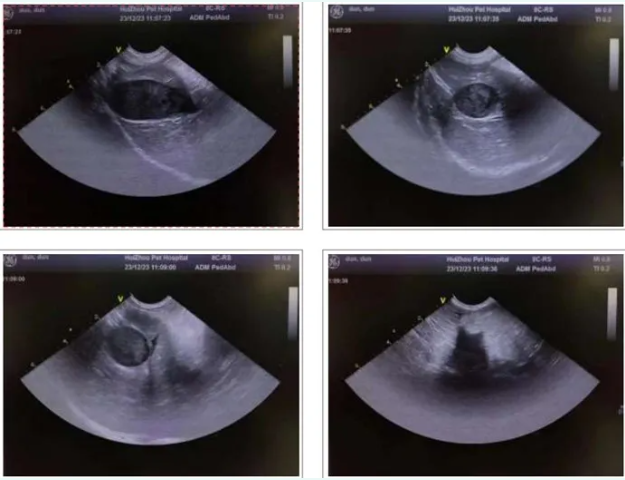

2.4 Ultraschall untersuchung

1. Die Gallenblase wand ist glatt, mit unklaren inneren Echos, und es wird keine offen sichtliche Erweiterung des Gallengangs beobachtet.

2. Die Leber ist normal in Form und Größe, mit einer glatten und kontinuier lichen Kapsel, homogener parenchym aler Echogenität und klaren intra hepa tischen röhrenförmigen Strukturen mit normalem Verlauf. Hypoecho ische Bereiche sind in den inter lobulären Räumen der Leber sichtbar.

3. Die Milz ist normal, aber vergrößert, mit homogenen Parenchym echos und einer leicht hypoecho artigen Masse, die darin sichtbar ist.

4. Die Größe und Form der Zwölffingerdarm birne, des absteigenden Segments und des horizontalen Segments sind normal und die Wände sind immer noch glatt. In keinem Teil des Zwölffingerdarms sind bestimmte Geschwüre oder Massen zu sehen, und es gibt keine Anzeichen von Zwölffingerdarm-Reflux.

5. Beide Nieren sind in Größe und Form normal, mit glatten und regelmäßigen Konturen, homogenen Parenchym echos, keinen raum greifenden Läsionen, keiner Trennung des Sammel systems, keiner Erweiterung eines Harnleiters und keinen offen sichtlichen abnormalen Echos in ihnen. Die Blase ist ausreichend gefüllt, mit glatten und durchgehenden Wänden und keinen offen sichtlichen abnormalen Echos in der Höhle. Ein mit Flüssigkeit gefüllter dunkler Bereich ist um die Blase herum sichtbar.

Basierend auf den Bildgebung sergeb nissen und der Urin analyze der gebildeten Elemente hatte der Hund keine Harn system erkrankung.Biochemische und Leber ultraschall ergebnisse schlossen Leber gelbsucht aus. Der Ultraschall der Gallenblase schloss eine Gelbsucht nach der Leber aus, was auf eine Gelbsucht vor der Leber hindeutet. Eine Masse wurde im Milz ultraschall gefunden; Blutabstrich-Screening zeigte keine Blut parasiten; und die Behandlung mit Blut transfusionen und Hormonen war unwirksam. Durch einen Elimination prozess wurde die Diagnose auf IMHA (intra zytoplasma tische Leber erkrankung) gerichtet.